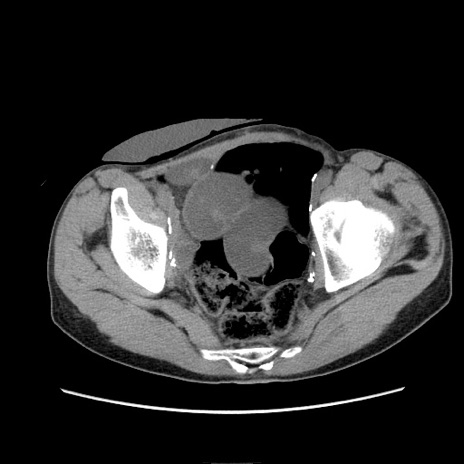

冠状断像

症例11(横断像)

【症例】 60歳代男性

【主訴】 下腹部痛

【現病歴】 本日夜中より下腹部痛の症状認め、受診。

【既往歴】 膀胱癌(膀胱全摘+尿管皮膚瘻術) 、胃癌術後

【身体所見】 BT 35.3℃、PR 58/min、BP 136/98mHg、腹部平坦、軟、腸蠕動音±、ストマ留置あり、左上腹部~正中部に圧痛あり、反跳痛なし。

【データ】WBC 5100、CRP0.01